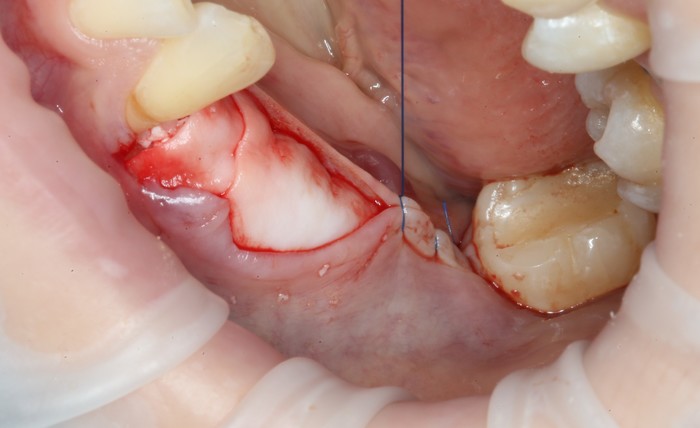

Уже на следующий день была запланирована имплантация.

Дабы не перегружать вас обилием одинаковых картинок, я оставлю один рентгеновский снимок, но отмечу, что установка имплантатов на верхней и нижней челюсти проводилась с разницей в 10 дней.

На верхней челюсти было дополнительно удалено два боковых резца с одномоментной установкой имплантатов, так же они были установлены в области четверок и шестых зубов. Дополнительно было проведено наращивание костной ткани - двусторонний синус - лифтинг. О том, что это такое, можно почитать ТУТ и ТУТ.